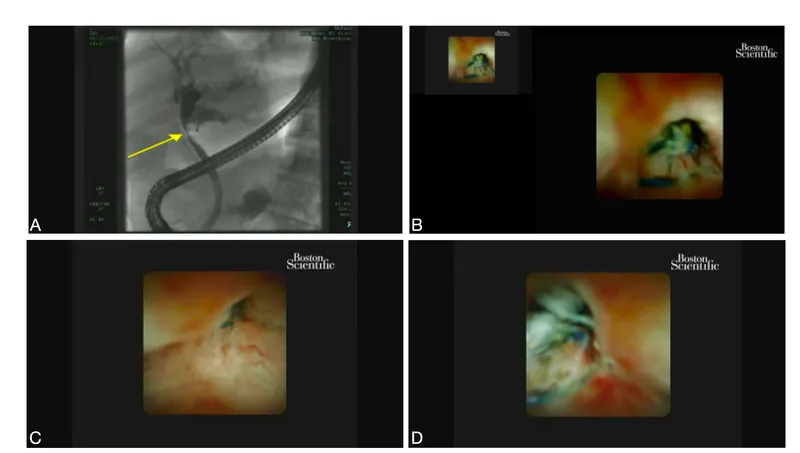

🔬 Biliary Spyglass (Cholangioscopy)

- Function: A single-operator cholangioscopy system used during ERCP for direct visualization of the biliary and pancreatic ducts. Enables targeted biopsies and therapy.

- Key Findings & Applications:

- Stones: Direct visualization of biliary stones; facilitates laser lithotripsy (e.g., Holmium laser) for large or impacted stones.

- Strictures: Differentiates benign from malignant.

- Malignant (Cholangiocarcinoma): Irregular, nodular, friable mucosa with abnormal, tortuous "tumor vessels."

- Benign: Smooth mucosa, symmetric narrowing, absence of neovascularity.

- Biopsy: Visually-guided forceps biopsy of indeterminate strictures or lesions.

⭐ Spyglass-guided biopsy significantly improves diagnostic yield for indeterminate biliary strictures over standard ERCP with brush cytology or random biopsies.